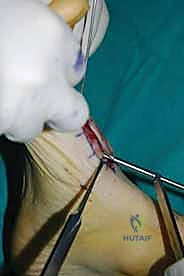

5. الترقيع العظمي (Bone Grafting) - عند الحاجة

في بعض الحالات التي يكون فيها فقدان عظمي كبير، أو لتعزيز فرص الالتحام، قد يتم أخذ طعم عظمي من منطقة أخرى من جسم المريض (مثل عظمة الساق أو الحوض)، أو استخدام بدائل العظام الاصطناعية (Allografts/Bone substitutes) لملء الفراغات بين العظام.